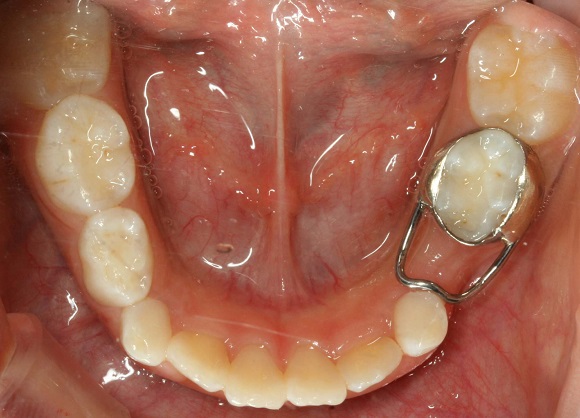

ㅊㅊ은

“유치를 미리 뽑으면 영구치가 빨리 나온다고 생각하는 경우가 있는데, 유치를 일찍 뽑으면 영구치가 나오는 속도가 느려지거나 나오는 방향이 바뀌게

되고, 정작 이와 빠진 치아 사이의 공간은 주변치아가 모이며 점점 사라지게 돼 영구치가 덧니가 되거나 아예 나오지 못하는 부정교합 증상이 나타날

수 있다”며 “검진을 꼼꼼하게 받으며 특히 ‘치아 사이의 충치’를 예방할 수 있도록 하고, 만약 충치 또는 외부적인 충격으로 유치가 일찍

빠졌다면 주변치아가 쓰러지지 않도록 공간유지장치를 이용해 영구치들이 제자리에 나올 수 있도록 유지해야만 한다”고 말했다.